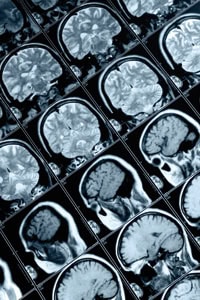

MRI scanners use helium-cooled superconducting magnets made from niobium alloys to generate strong fields (1-2 Tesla) that line up the spins of hydrogen atoms in the body. Radio frequency fields are then used to systematically alter the alignment of this magnetisation. This produces an oscillating magnetic field detectable by the scanner, and this information is recorded to construct an image of the scanned area of the body. The technology has revolutionised the detection of diseased tissues such as brain tumours, however the maintenance of their superconductive magnets has driven the costs of MRI machines into millions of pounds, limiting their use in the financially-constrained healthcare environment.

In response, manufacturers have developed less expensive, low-magnetic-field-strength (0.2 Tesla and below) MRI scanners. Most of the cost saving comes from using an electromagnet instead of a superconducting one, however, the lower field strength results in poorer quality images and longer scan times.